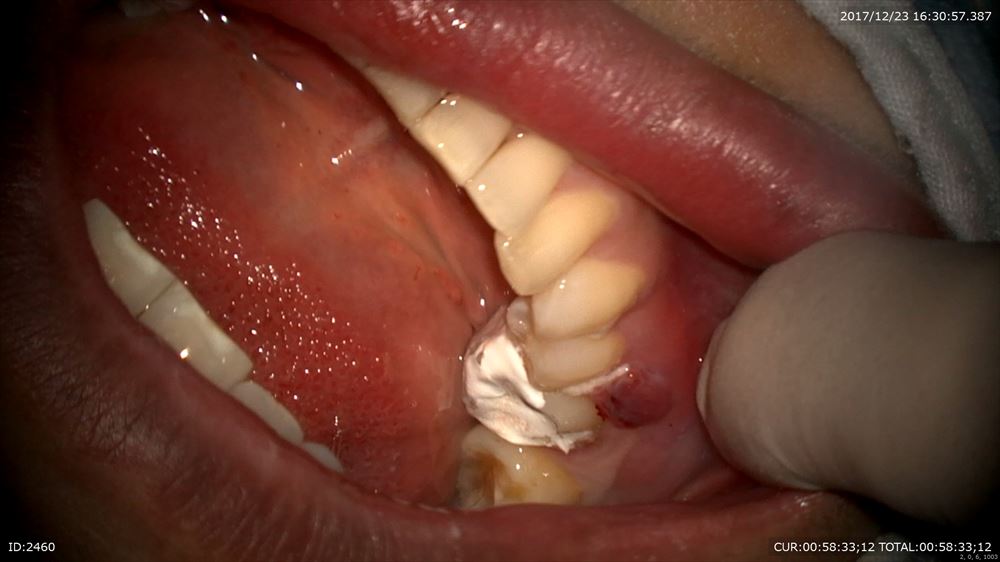

神経保存のケース

右上5番神経が見えるほどの虫歯

MTAで保存して11月から症状を確認し本日修復。きょうから咬めます!